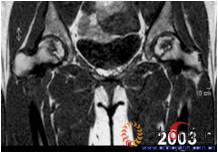

图1 女,22岁,(1)双侧股骨头坏死右侧B型,左侧C1型;(2)打压植骨术(加入BMP2)后5年,CT显示植骨生长良好,关节功能正常(Harris评分96分);(3)术后7年关节功能维持正常,股骨头维持正常外形